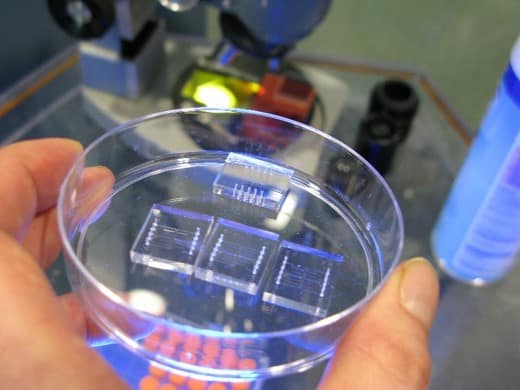

A cataract-affected eye scatters and refracts light before it reaches the retina, caused by a fogging or clouding of the lens. This system measures this deformation, or clouding, by allowing one to compare a good light path with a light path blocked by the cataract.

Current methods for cataract detection require costly equipment and highly trained clinicians. Traditional techniques measure back-scattering, which is observed and subjectively diagnosed, but do not address the early onset of cataract affected vision as early opacities are difficult to detect, especially in the field. Back-scattering can also be misleading as it does not account for what the patient actually sees. This novel approach, reduced here to practice, captures a full map of opacity and scattering, providing significant improvements beyond existing techniques which are limited to a simple grading of severity.